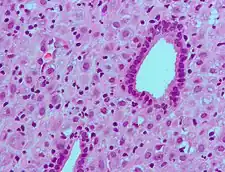

(A) proliferative endometrium (Left: HE × 400) and proliferative endometrial cells (Right: HE × 100)

(B) secretory endometrium (Left: HE × 10) and secretory endometrial cells (Right: HE × 10)

(C) atrophic endometrium (Left: HE × 10) and atrophic endometrial cells (Right: HE × 10)

(D) mixed endometrium (Left: HE × 10) and mixed endometrial cells (Right: HE × 10)

(E): endometrial atypical hyperplasia (Left: HE × 10) and endometrial atypical cells (Right: HE × 200)

(F) endometrial carcinoma (Left: HE × 400) and endometrial cancer cells (Right: HE × 400).